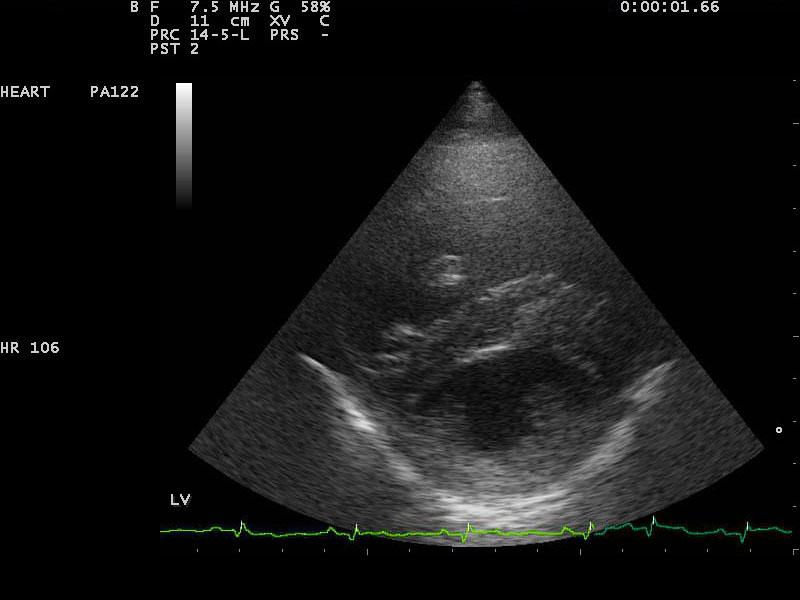

A 10-year-old SF Labrador was presented for evaluation of ascites, which was quantified as a modified transudate. Additional history on this dog was that 11 months prior an ovariohysterectomy and resection of mammary gland tumors had been done. The tumors were benign on histopathology. On abdominal ultrasound, the ascites, hepatic congestion, and a dilated CVC were present.